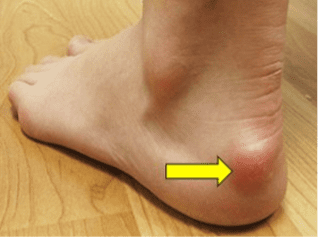

A deformidade de Haglund é um aumento ósseo anormal na região posterossuperior do calcâneo, onde o tendão do calcâneo se insere. Essa protuberância pode ser facilmente visualizada (ver Figura 1) e palpável durante o exame físico.

Tenho certeza de que todos nós já observamos essa condição em nossa população de pacientes. Essa deformidade foi descrita pela primeira vez pelo cirurgião ortopédico sueco Patrick Haglund em 1927. Essa condição também é conhecida como exostose retrocalcânea, deformidade de Mulholland e “inchaço em bomba”. O inchaço ósseo pode causar irritação do tendão calcâneo distal e das bursas adjacentes.